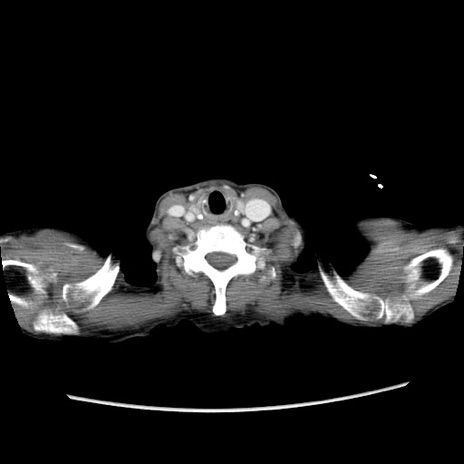

症例25(横断像)

【症例】80歳代女性

【主訴】胸のつかえ感

【現病歴】約9時間前に食後から胸のつかえた感じあり、嘔吐あり、来院。

【既往歴】胃癌(全摘)、胆摘、虫垂炎

【身体所見】心窩部に圧痛あり、反跳痛なし。

【データ】WBC 5700、CRP 0.05